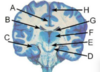

State what type of herniation A-D are [4]

A: **Cingulate** (Subfalcine) B: **Central** (**transtentorial**) C: **Uncal** D: Downward cerebellar (**Tonsillar**)